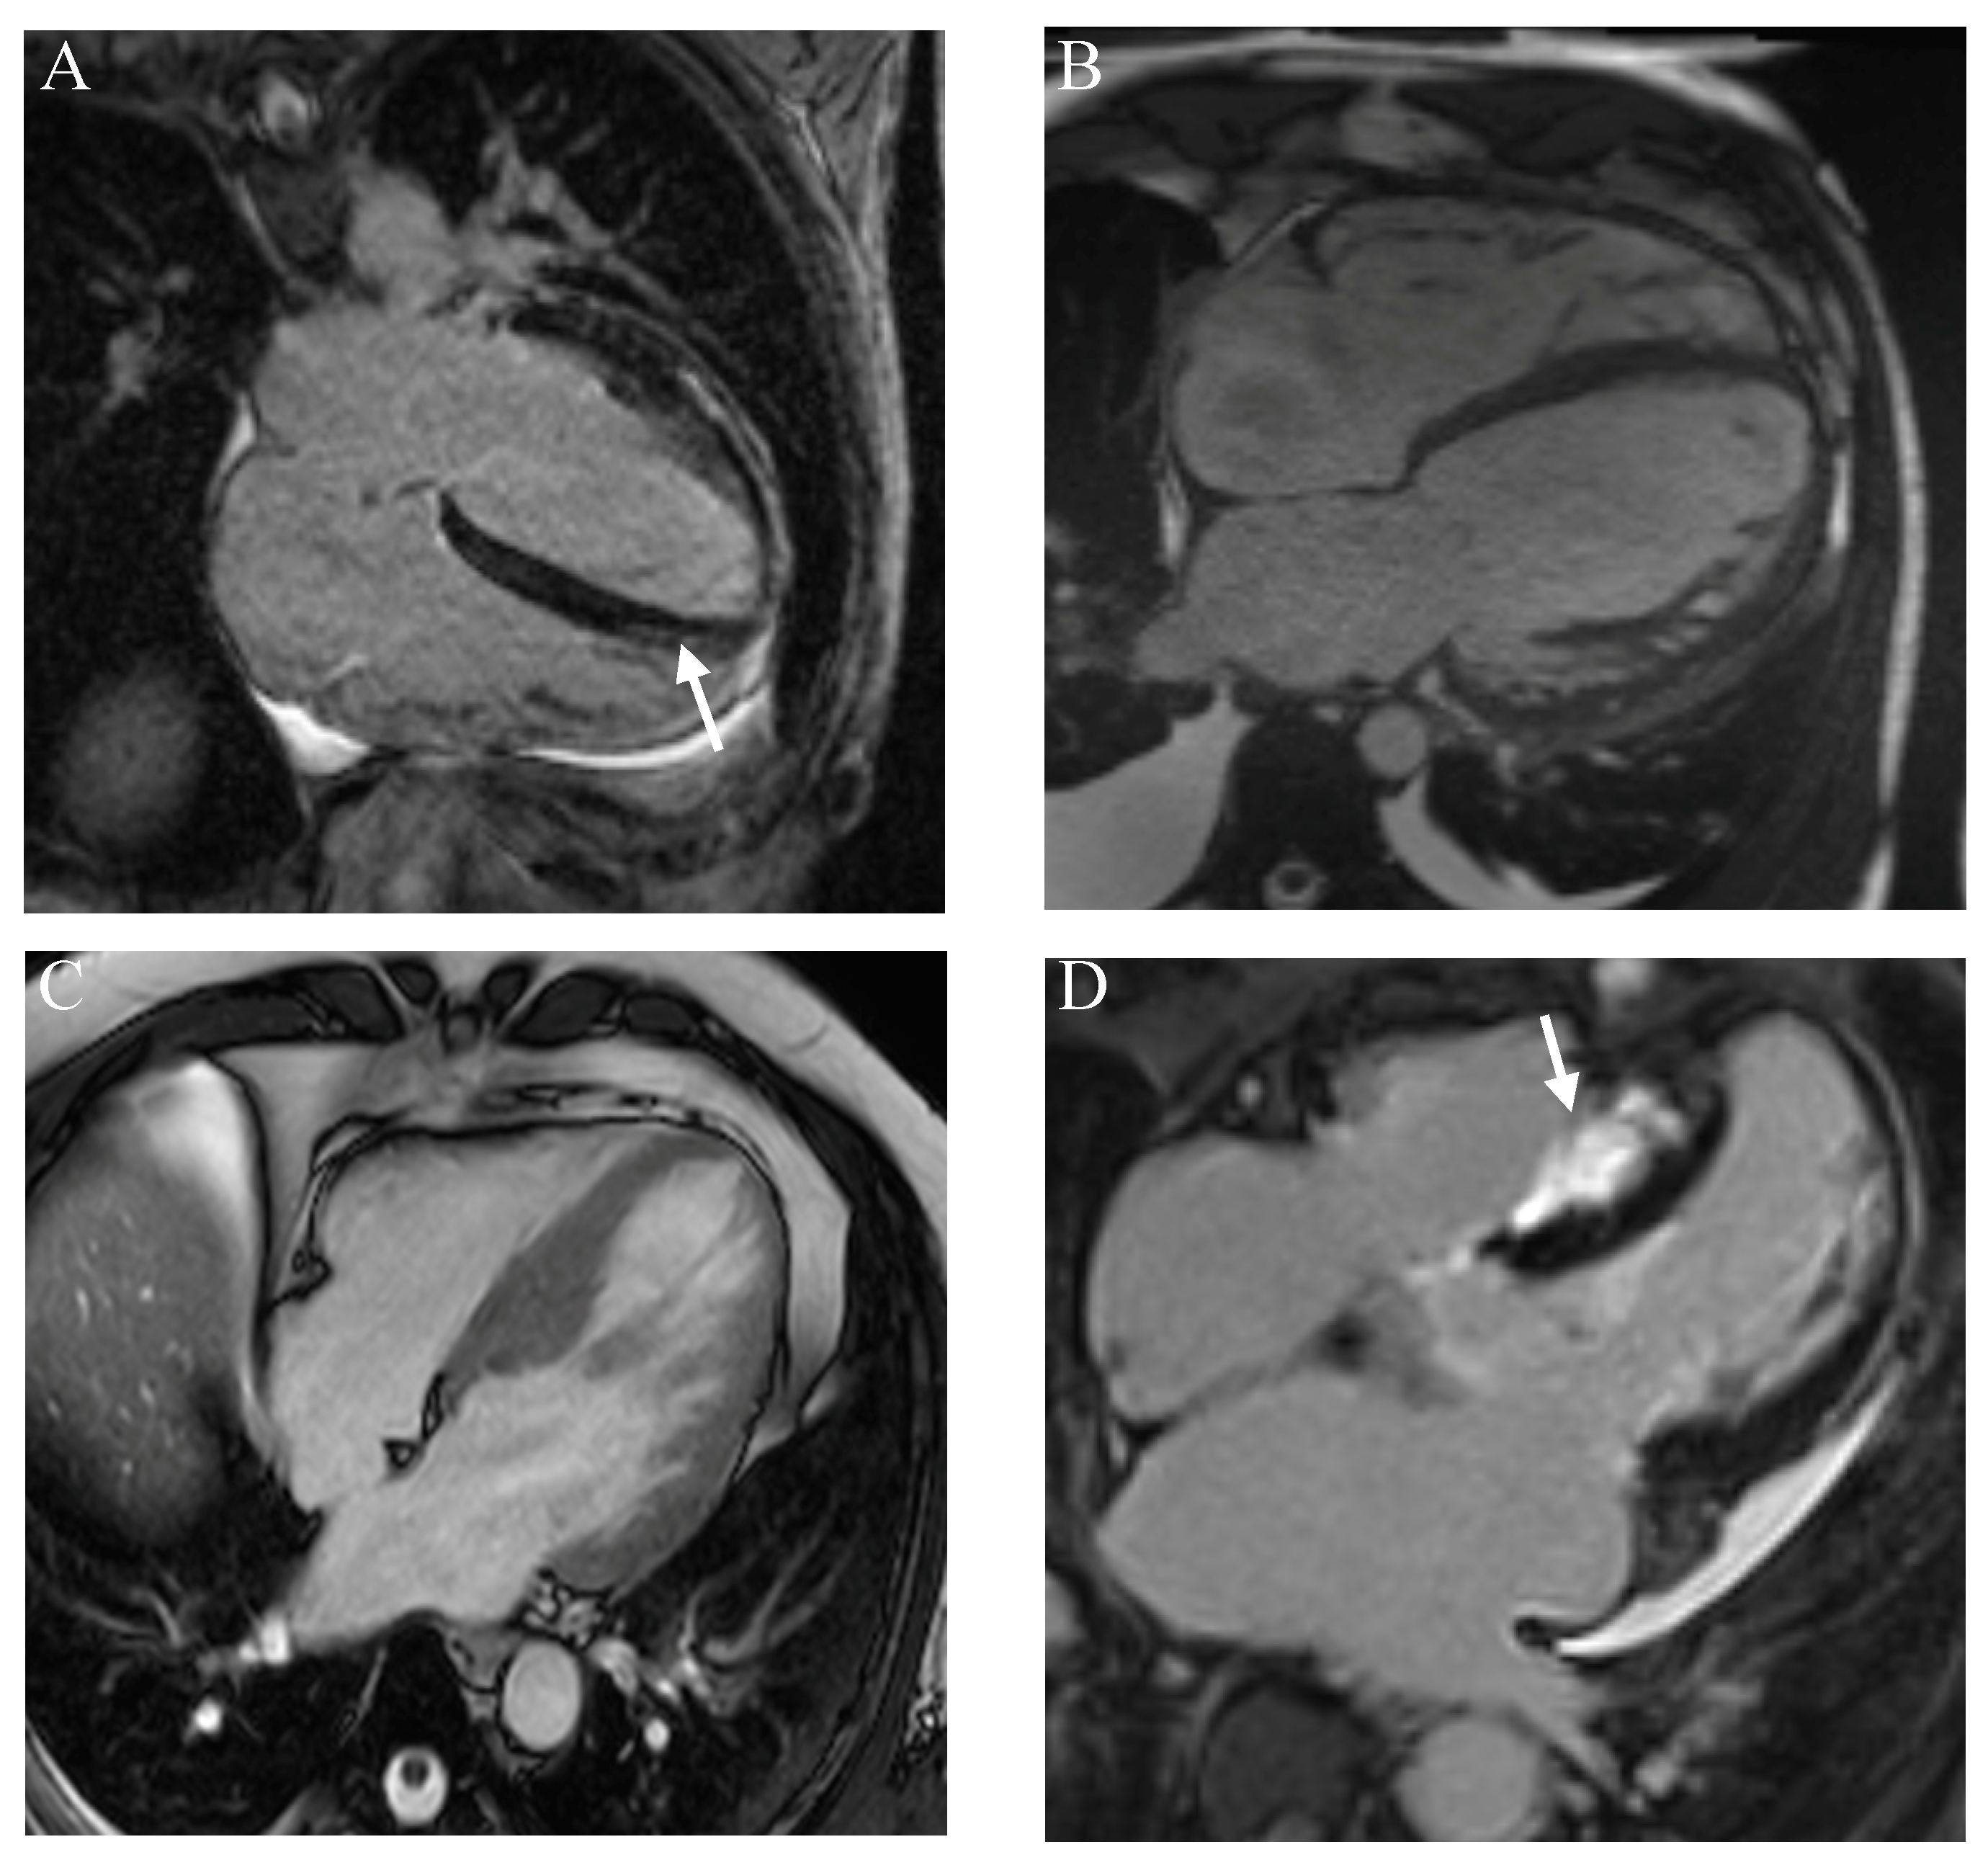

- Marschner, C.A.; Aloufi, F.; Aitken, M.; Cheung, E.; Thavendiranathan, P.; Iwanochko, R.M.; Balter, M.; Moayedi, Y.; Duero Posada, J.; Hanneman, K. Combined FDG PET/MRI versus Standard-of-Care Imaging in the Evaluation of Cardiac Sarcoidosis. Radiol. Cardiothorac. Imaging 2023, 5, e220292. [Google Scholar] [CrossRef]

- Kurashima, S.; Kitai, T.; Xanthopoulos, A.; Skoularigis, J.; Triposkiadis, F.; Izumi, C. Diagnosis of cardiac sarcoidosis: Histological evidence vs. imaging. Expert. Rev. Cardiovasc. Ther. 2023, 21, 693–702. [Google Scholar] [CrossRef]

- Hervier, E.; Glessgen, C.; Nkoulou, R.; François Deux, J.; Vallee, J.P.; Adamopoulos, D. Hybrid PET/MR in Cardiac Imaging. Magn. Reson. Imaging Clin. N. Am. 2023, 31, 613–624. [Google Scholar] [CrossRef]

- Shrivastav, R.; Hajra, A.; Krishnan, S.; Bandyopadhyay, D.; Ranjan, P.; Fuisz, A. Evaluation and Management of Cardiac Sarcoidosis with Advanced Imaging. Heart Fail. Clin. 2023, 19, 475–489. [Google Scholar] [CrossRef]

- Puntmann, V.O.; Isted, A.; Hinojar, R.; Foote, L.; Carr-White, G.; Nagel, E. T1 and T2 Mapping in Recognition of Early Cardiac Involvement in Systemic Sarcoidosis. Radiology 2017, 285, 63–72. [Google Scholar] [CrossRef]

- Pöyhönen, P.; Nordenswan, H.K.; Lehtonen, J.; Syväranta, S.; Shenoy, C.; Kupari, M. Cardiac magnetic resonance in giant cell myocarditis: A matched comparison with cardiac sarcoidosis. Eur. Heart J. Cardiovasc. Imaging 2023, 24, 404–412. [Google Scholar] [CrossRef]